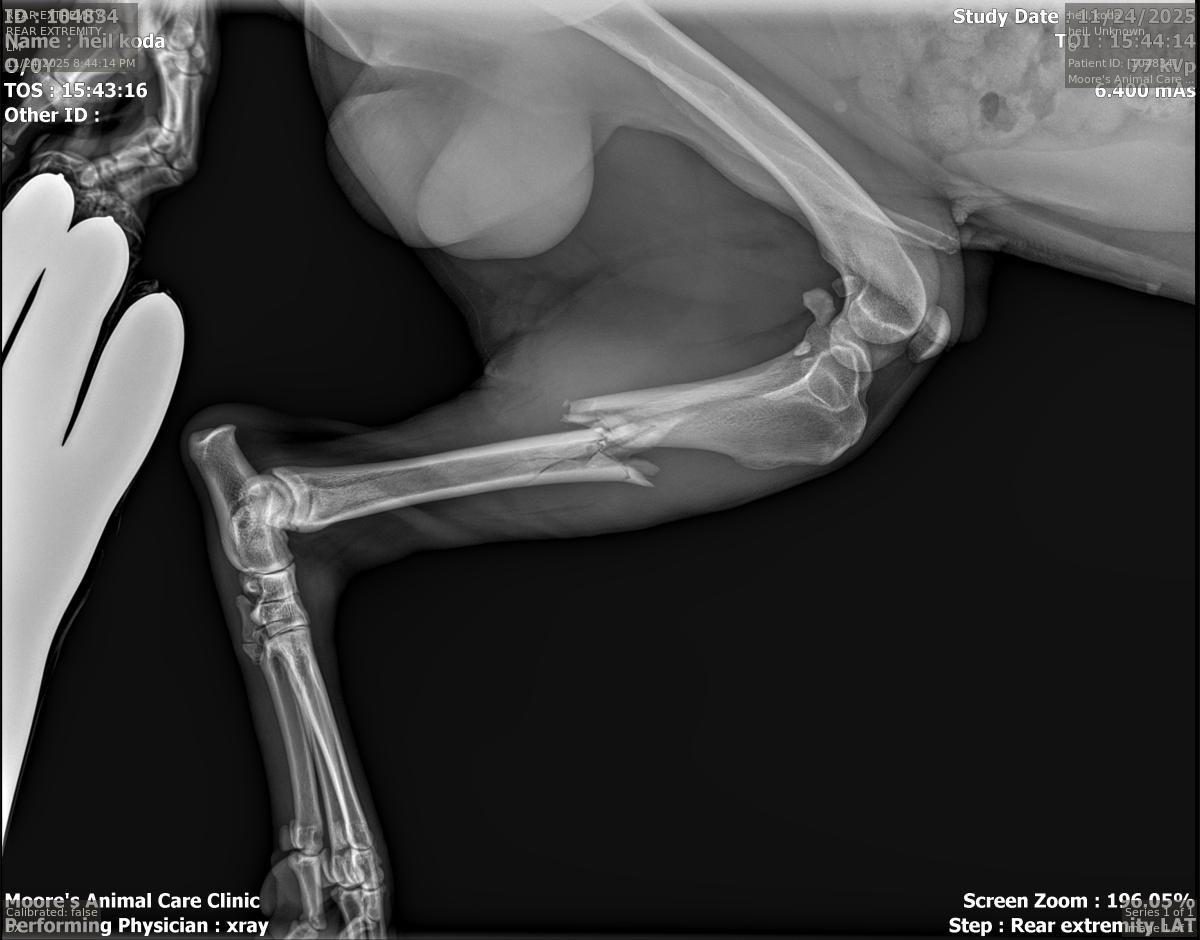

Our sweet boy, Koda, was missing for 8 days. When he finally came home, we could tell right away that something was wrong. His leg was badly broken—fractured all the way down the bone—and he had clearly been through a lot trying to make his way back to us.

After taking him to the vet, we learned that the only way to save his leg is with major surgery. A metal rod has to be placed inside the bone for it to heal properly. Without this procedure, Koda may never regain full use of his leg.

The vets believe he was likely hit by a car. We don’t know how long he struggled before he got home, but we’re grateful he made it back safely.